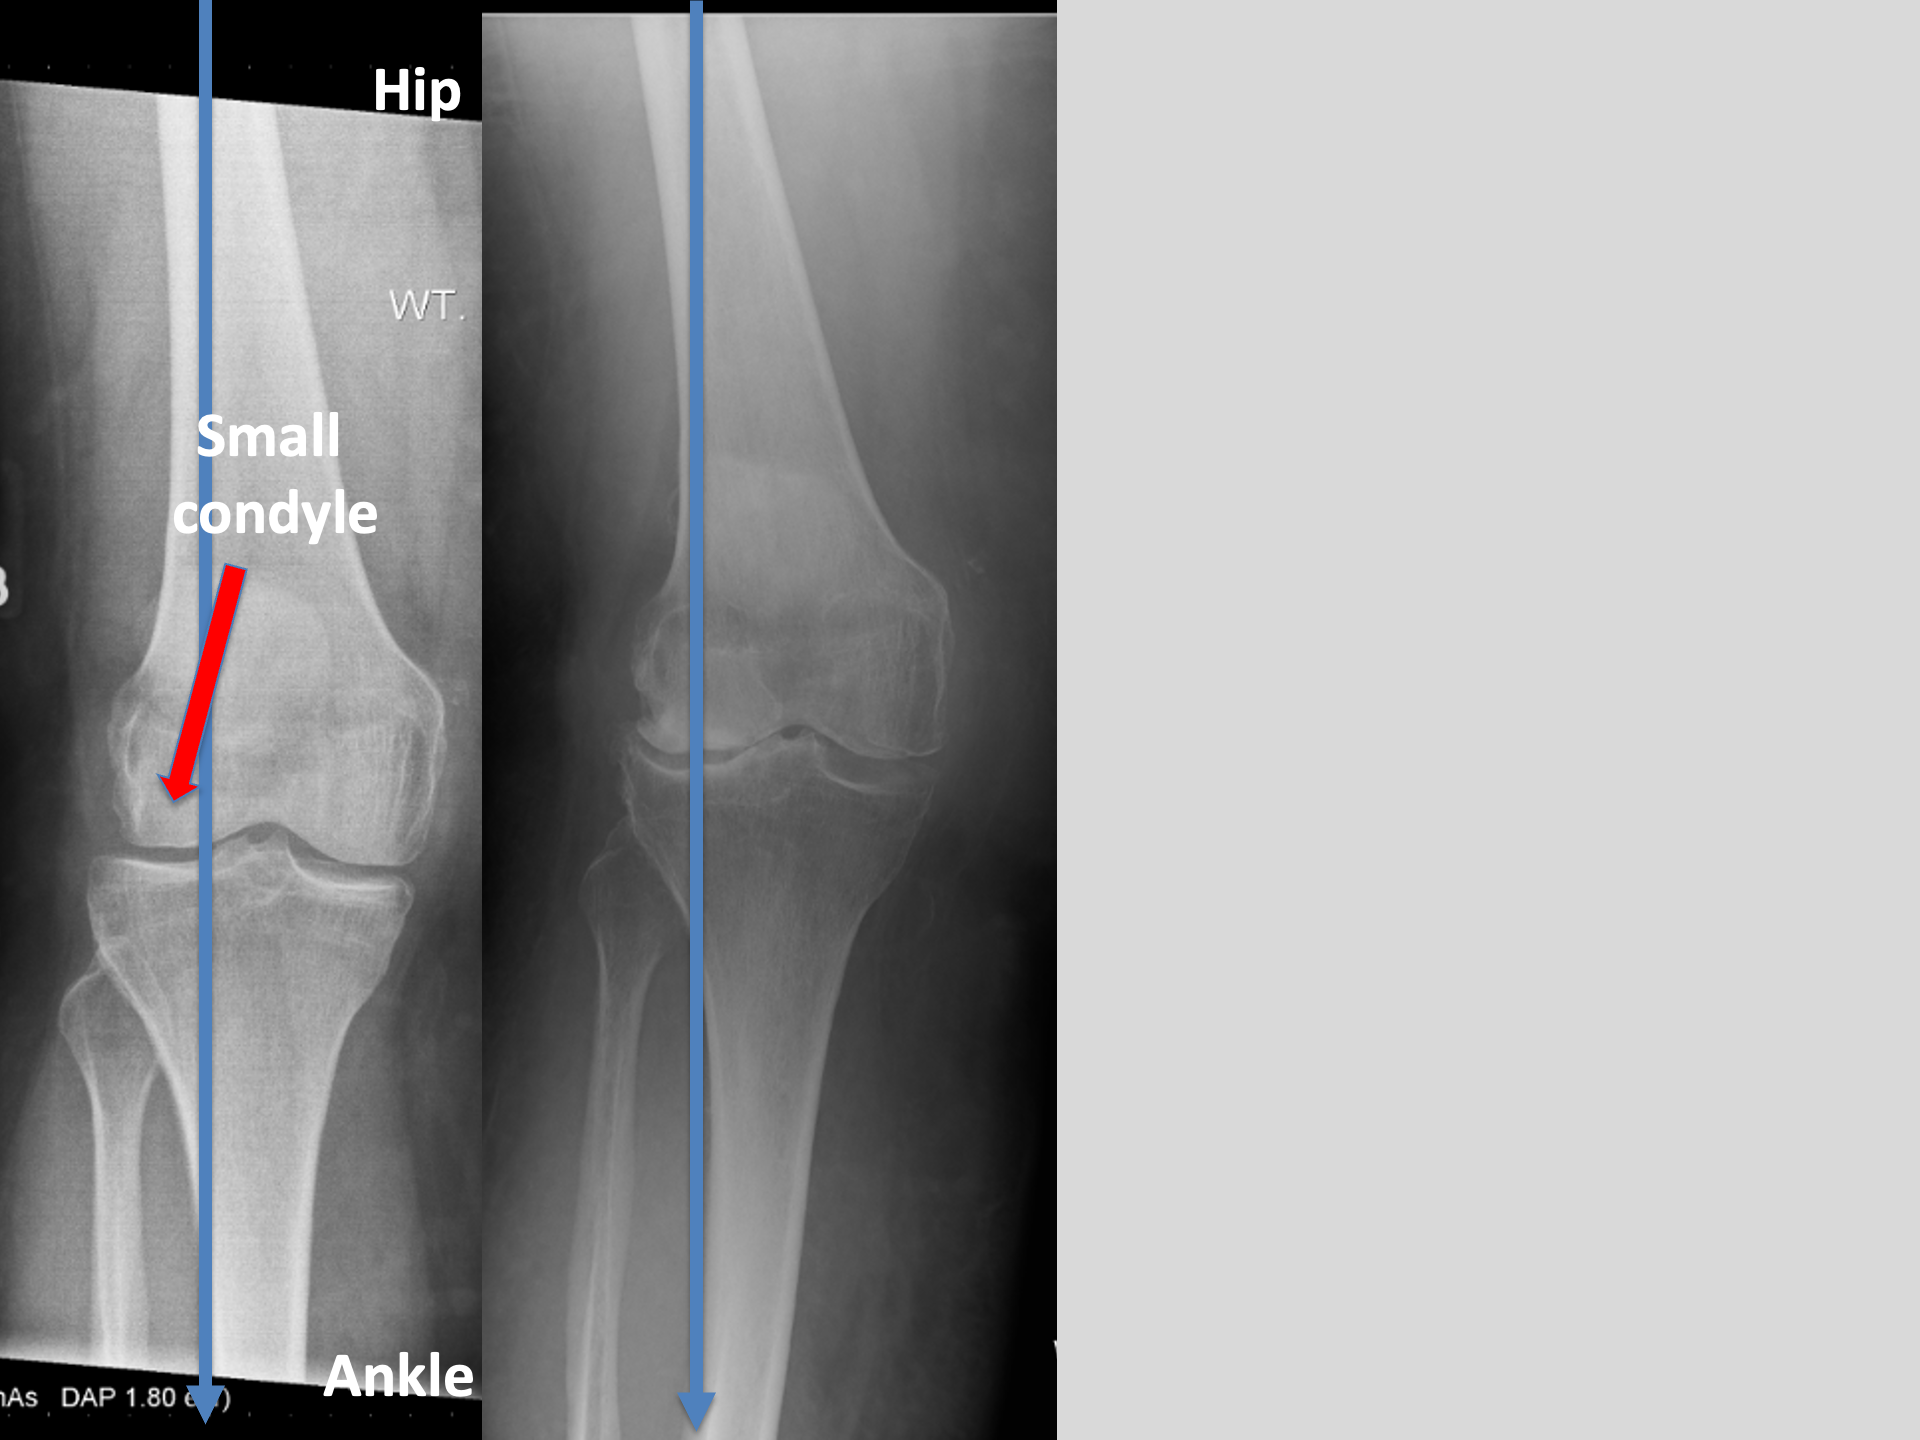

That blue line is way out to the outside of Marie's right knee

Every step is jamming all the force through the outside of her knee.

Inflammation. Pain. And now, a feeling of Instability..

Her knee felt like it was going to give way with every step.